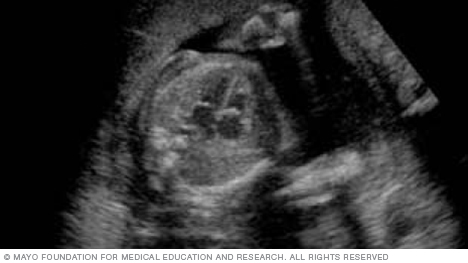

The image below shows all four chambers of the heart, as well as the heart valves. This type of image usually is taken during an ultrasound done between weeks 18 and 22 of pregnancy. Fetal ultrasound is used to check that the heart is working properly and to see if there could be any heart problems.